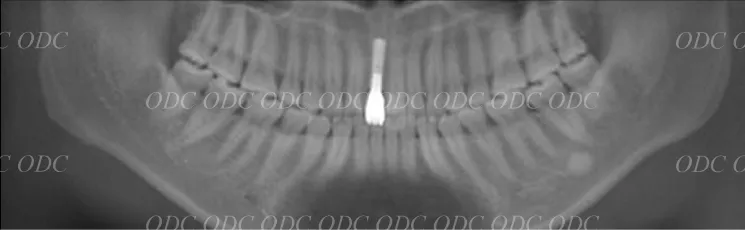

前歯がもともと4本、生えてこなかった症例。

インプラント治療を希望。

顎位(噛み合わせ)を正し、矯正治療にて歯を移動させる。

コンピューターで計画を行い、上部構造に関してもコンピューターにてデザイン。

最終物が装着されるまでに第1のプロビジョナルレストレーション(上段)と第2のプロビジョナルレストレーションを装着。

最終の補綴物が装着された、口腔内写真とレントゲン写真。